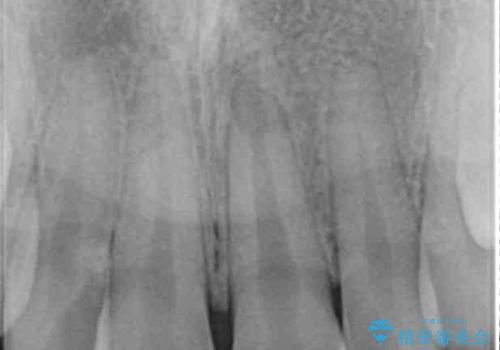

- 変色した前歯と突出した口元を気にして来院された患者様です。

口元の突出感はインビザラインにより歯列を整え、その後に、前歯をオーダーメイドタイプのオールセラミッククラウンにて補綴治療することとしました。